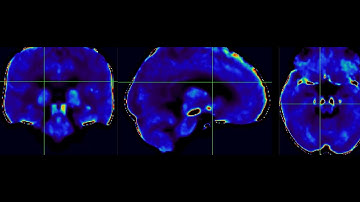

Myelin Imaging Using 3D Dual-echo Ultra-short Echo Time MRI with Rosette k-Space Pattern